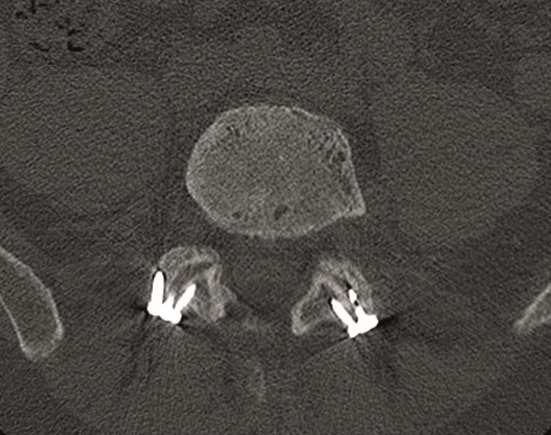

A less invasive approach was used with Insight Retractor using the bilateral Facet Wedge. No bone graft. X-ray follow-up after 3 months and CT assessment after 6 months (Fig 18-19).